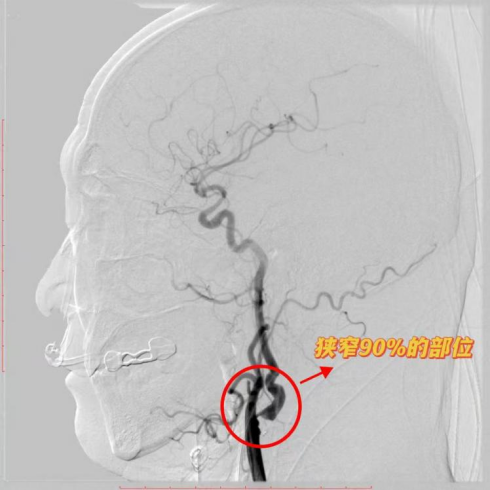

济南南郊医院成功完成复杂颈动脉狭窄手术 为高难度脑血管病治疗树立新标杆

近日,济南南郊医院脑科团队成功为一名61岁男性患者实施高难度颈动脉内膜斑块切除术,帮助患者摆脱脑卒中高风险威胁。